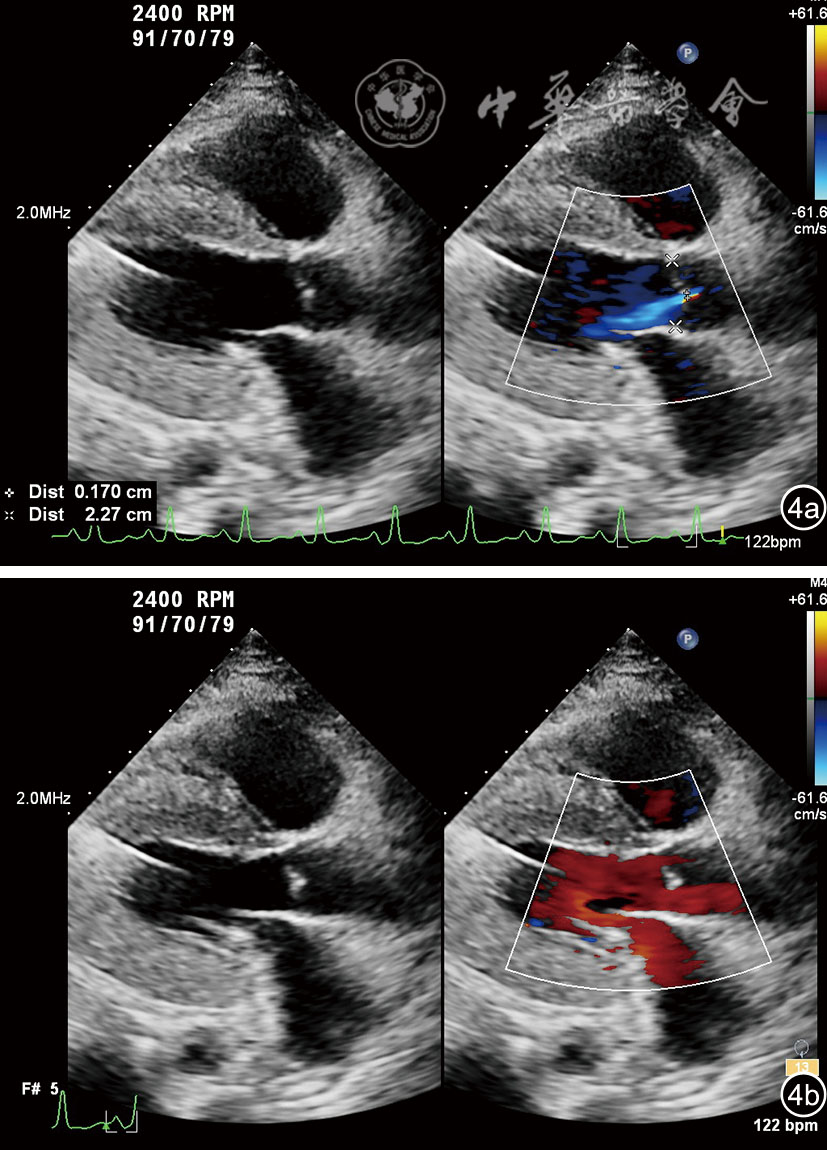

图4 左心室辅助装置植入术后主动脉瓣反流超声图像。图a示胸骨旁左心室长轴切面,收缩期少量主动脉瓣反流;图b示舒张期主动脉瓣反流消失

图5 M型彩色多普勒显示收缩期主动脉瓣反流(黄色箭头所示)